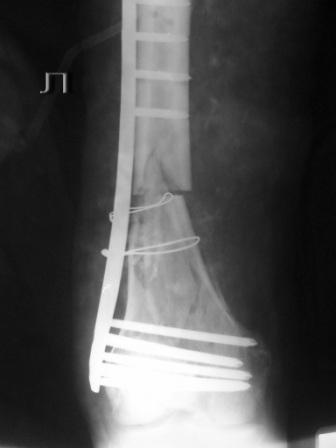

Пациенту 50 лет. 24.11.09 сделали л\бедро.

Оставлен клинически значимый варус, видно градусов 8-10. Для уточнения можно сделать снимок симметричного сегмента и скиаграммы наложить.

Не стоило открывать промежуточные отломки и вязать их проволокой. Это ухудшает их кровоснабжение и может привести к несращению. Не во все случаях, конечно. Удачи.

Сложность репозиции привела к "освобождению" промежуточных отломков - появился значительный костный дефект - пришлось создавать картинку + добавили коллапан.

Мостовидность это только часть , так называемого, биологического принципа.Биологический принцип предполагает баланс между механическими свойствами остеосинтеза и сохранением кровоснабжения кости и окружающих мякких тканей. Мостовидная фиксация обеспечивает относительную, эластичную стабильность, которая при малоинвазивной технике (MIPO), т.е, при закрытой репозиции и нескелетировании кости дает хороший шанс на быстрое течение репаративных процессов и сращение перелома.

В Вашем примере, как мне кажется, была довольно травматичная открытая реползиция со скелетированием концов перелома. В результате отсутствует необходимая биологическая составляющая для нормальной репарации кости. кроме того, положение отломков по оси - так себе, и имеется значимый медиалный дефект. Так что к био-логической мостовидной технике фиксации переломов этот случай не имеет никакого отношения. Увы(